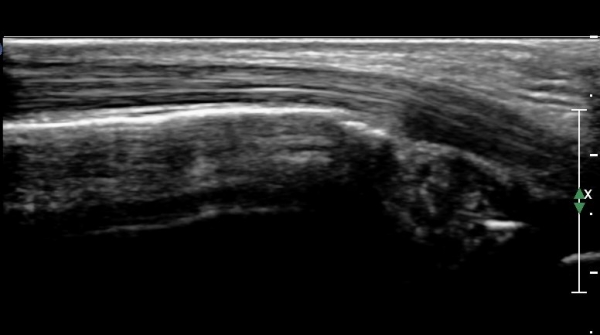

Àü°ÅºñÀδë Á¾´Ü¸é°Ë»ç»ó Àü°ÅºñÀδëÀÇ Àú¿¡ÄÚ À§Ãà°ú Á·±Ùµ¿(sinus tarsi) ¼ö¾×Àú·ù°¡

°üÂûµÈ´Ù(»çÁø 2, 3).